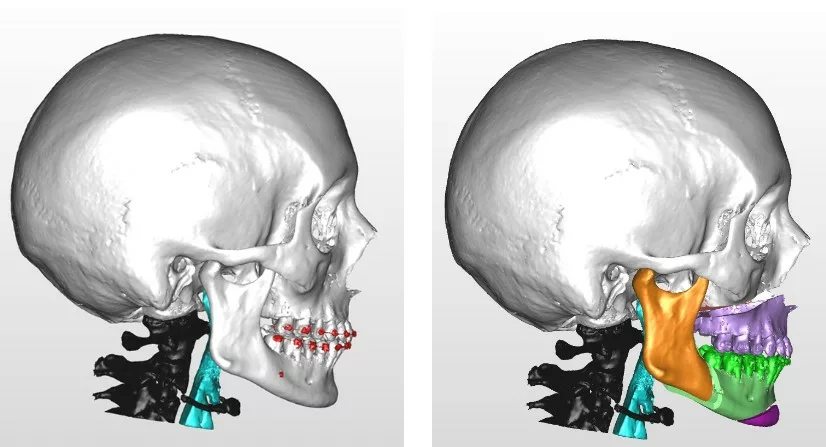

Chirurgie orthognathique

Classe III